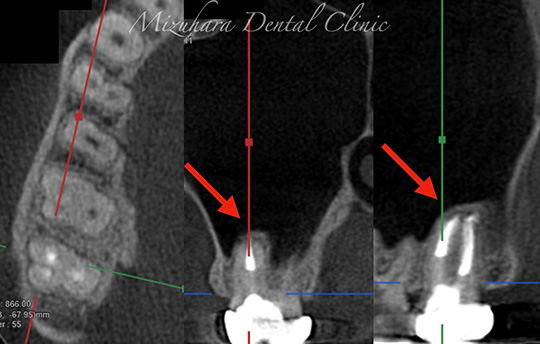

保存可能な歯を見極め

予知性の高い治療を提供できるだけ患者様の大切な歯を残し、10年、20年先まで健康な状態を保てるよう、長期的な視点で治療を計画します。そのために最も重要なのが、「診査」と「診断」です。的確な診断は精密な診査から生まれ、治療結果を大きく左右します。問診や簡易検査だけでは見逃されがちな病変も、CTやマイクロスコープなどの最新の医療機器を活用し、時間をかけて丁寧に「診査・診断」を行います。